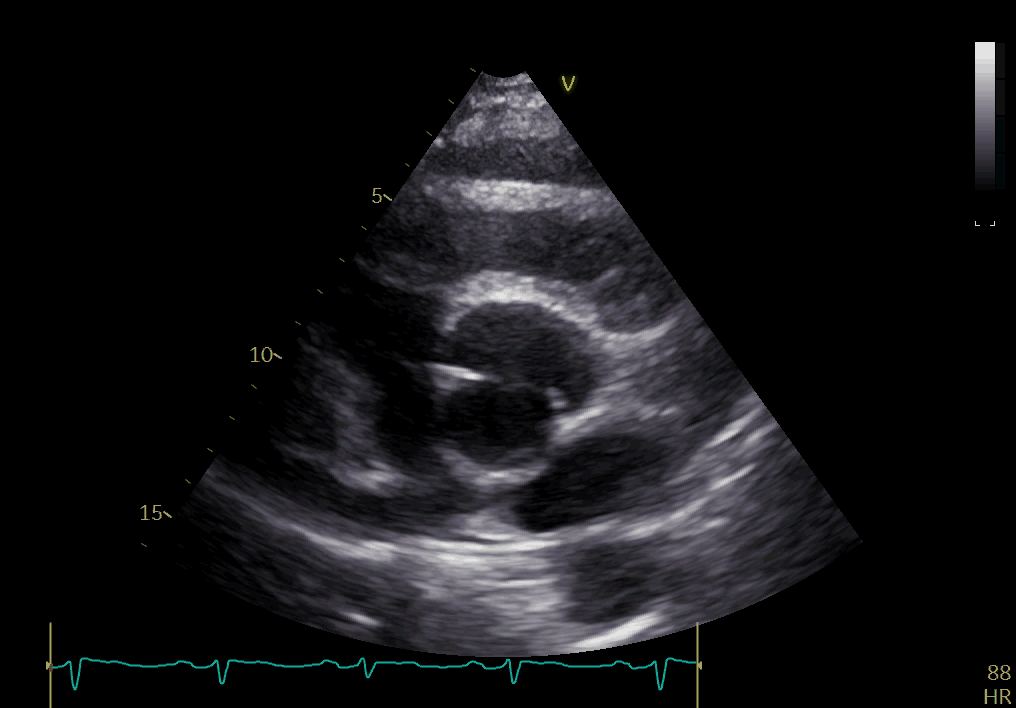

加重1年入院,超声心动图提示主动脉瓣重度狭窄,左室壁肥厚,节段性室壁(3)

左室射血分数减低(ef 32%);二尖瓣轻度返流;三尖瓣轻度返流;主动脉瓣

左室射血分数(lvef)45%,节段性室壁运动减低;左房增大;主动脉瓣轻度反

三尖瓣反流频谱示肺动脉收缩压约57 mmhg,平均压约40 mmhg,提示肺